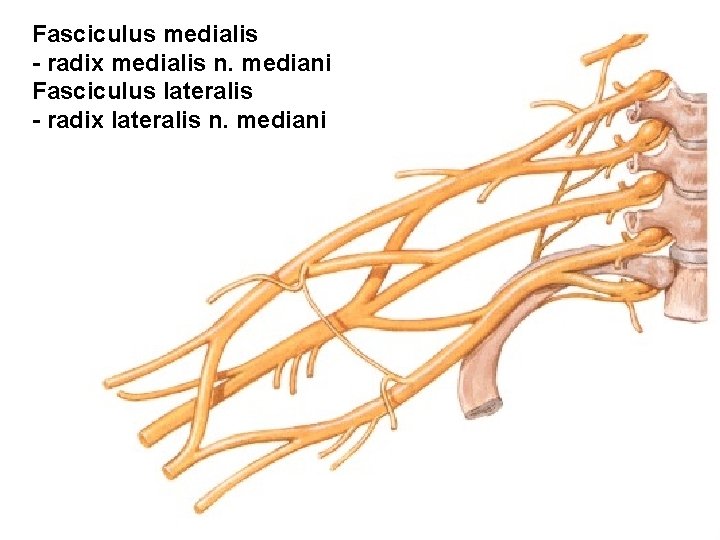

Fasciculus medialis - radix medialis n. mediani Fasciculus lateralis - radix lateralis n. mediani

N. MEDIANUS

N. MEDIANUS (Sulcus bicipitalis medialis)